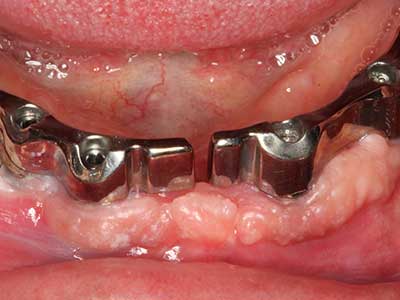

Fig. 15: El control radiológico realizado al cabo de un año muestra una estabilidad del nivel óseo.

Fig. 16: También condiciones intraorales estables con incorporación de los implantes en la encía queratinizada.